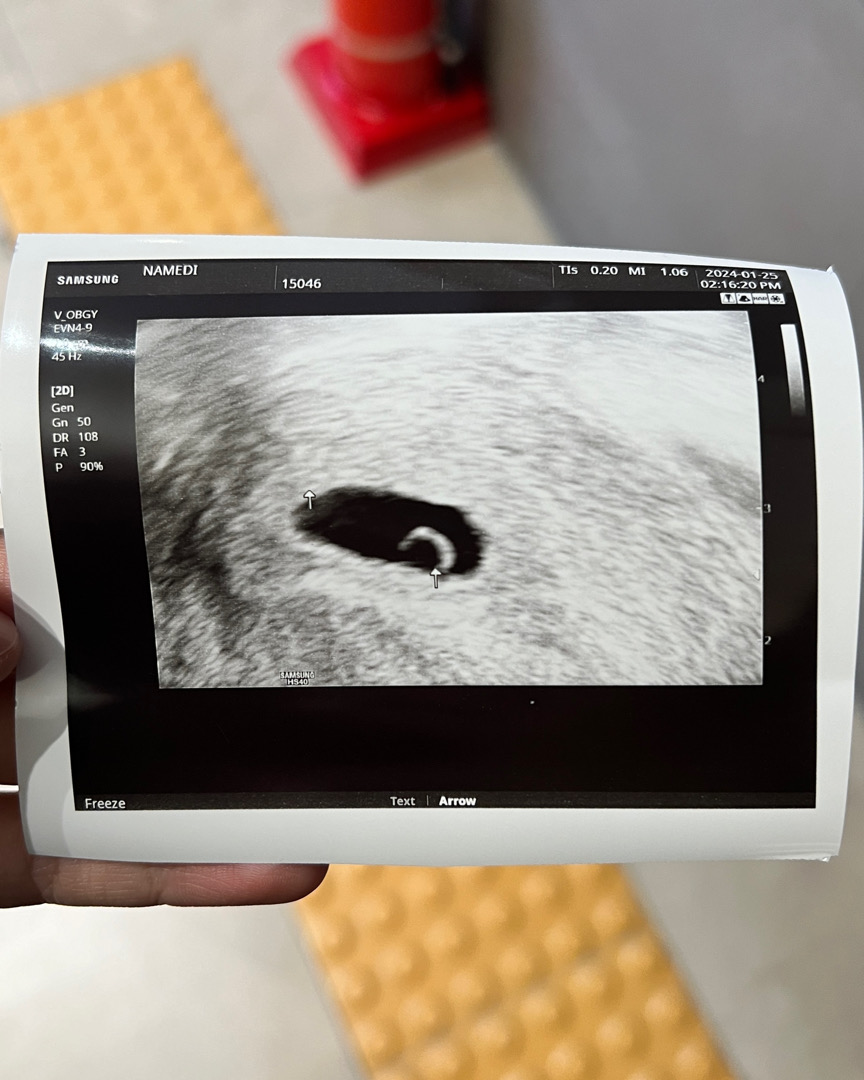

5주4일 반짝반짝 난황 보고 왔어요!

5주0일에 아기집 보고 다음 검진은 다음주인데, 오늘 역대급 소화불량으로 가스 차고 복통이 너무 심해 걱정되서 초음파 보고 왔어요! 다행히 제 증상은 지극히 자연스러운거고 아기에게 해롭지 않다고 하네요 :)